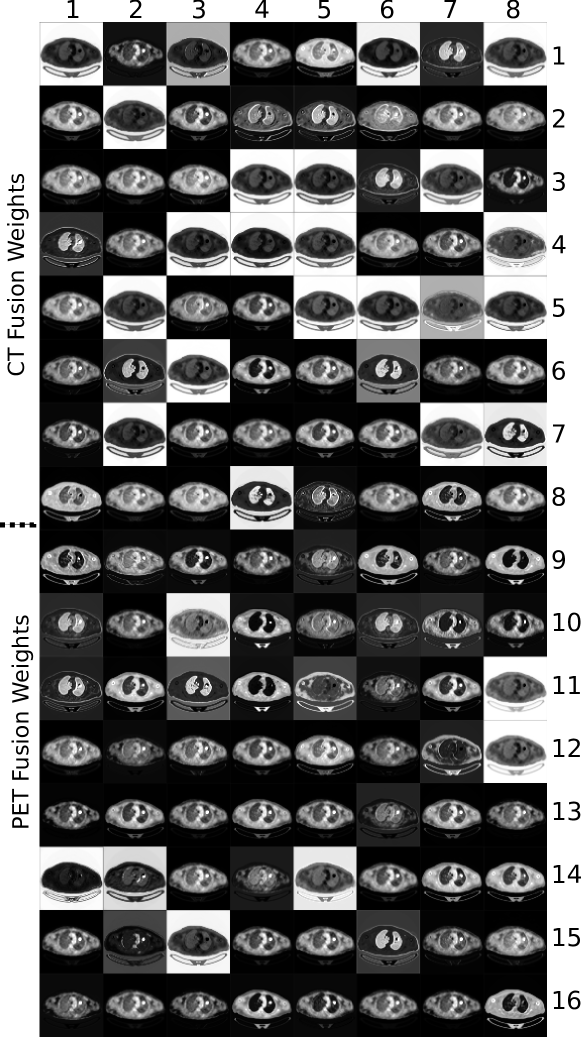

Fig. 7 depicts the co-learned fusion maps that were derived for an image with a single tumor; a larger version is included as Fig. S5 in the Supplementary Materials. In the figure, each feature map channel has been independently normalized so that their real valued pixels could be viewed in the paper. In any particular channel, a higher absolute intensity implies a greater importance placed on that pixel during fusion. The figure shows how different information is prioritized differently for each region. For example, the 7th CT fusion channel (row 1, column 7) places a greater emphasis on the lungs while the 26th PET fusion channel (row 8, column 2) places the greatest emphasis on the tumor. The figure also indicates that the fusion weights are derived from features of both modalities. For example, the 7th CT fusion channel (row 1, column 7) emphasizes the lungs including the area that contains the tumor. Meanwhile, the 13th CT fusion channel (row 2, column 5) also emphasizes the lungs but de-emphasizes the area containing the tumor. Further analyses are included in Section SIII of the Supplementary Materials.

The fusion maps shown in Fig. 7 demonstrate that our co-learning CNN can derive spatially varying fusion maps for images that contain multiple structures that have different fusion requirements. Our CNN does not need to divide the problem into distinct tasks for each ROI but rather can derive the relevant fusion information in an end-to-end manner. For example, the 7th CT fusion channel (row 1, column 7) and the 13th CT fusion channel (row 2, column 5) emphasize the lung fields relative to the area containing the tumor. We suggest the co-learning unit has produced these specific fusion channels because (in combination with other channels) they contain information to distinguish the lung fields from any tumors they may contain. It is well-established that the lung fields can be identified using CT data alone [57], and it was expected that the co-learning CNN would operate in a similar fashion. The fusion maps automatically derived by our co-learning CNN prioritize the CT data for the lung field ROIs, consistent with this expectation. Similar patterns for lung fields are noticed in the fusion maps of other PET-CT images.

While it may appear that several channels in the fusion map are redundant (similar in appearance to other channels), this is merely a visualization issue caused by normalizing 32-bit floating point greyscale images for display within the paper. As shown in Fig. S4 in the Supplementary Materials, PET fusion channels 33 to 37 (row 13, columns 1 to 5) appear visually similar but closer examination of the distribution of fusion weights within the images indicates that each channel prioritizes information in subtly different ways. Section SIII in the Supplementary Materials contains a detailed example showing the differences in these visually similar fusion channels and their impact in the analysis of heterogeneous tumors, which is an important clinical application. We suggest that the capacity of our co-learning CNN to derive these subtly different fusion weights enables more precise integration of the complementary information in each modality when compared with uniform fusion (see Fig. 8).